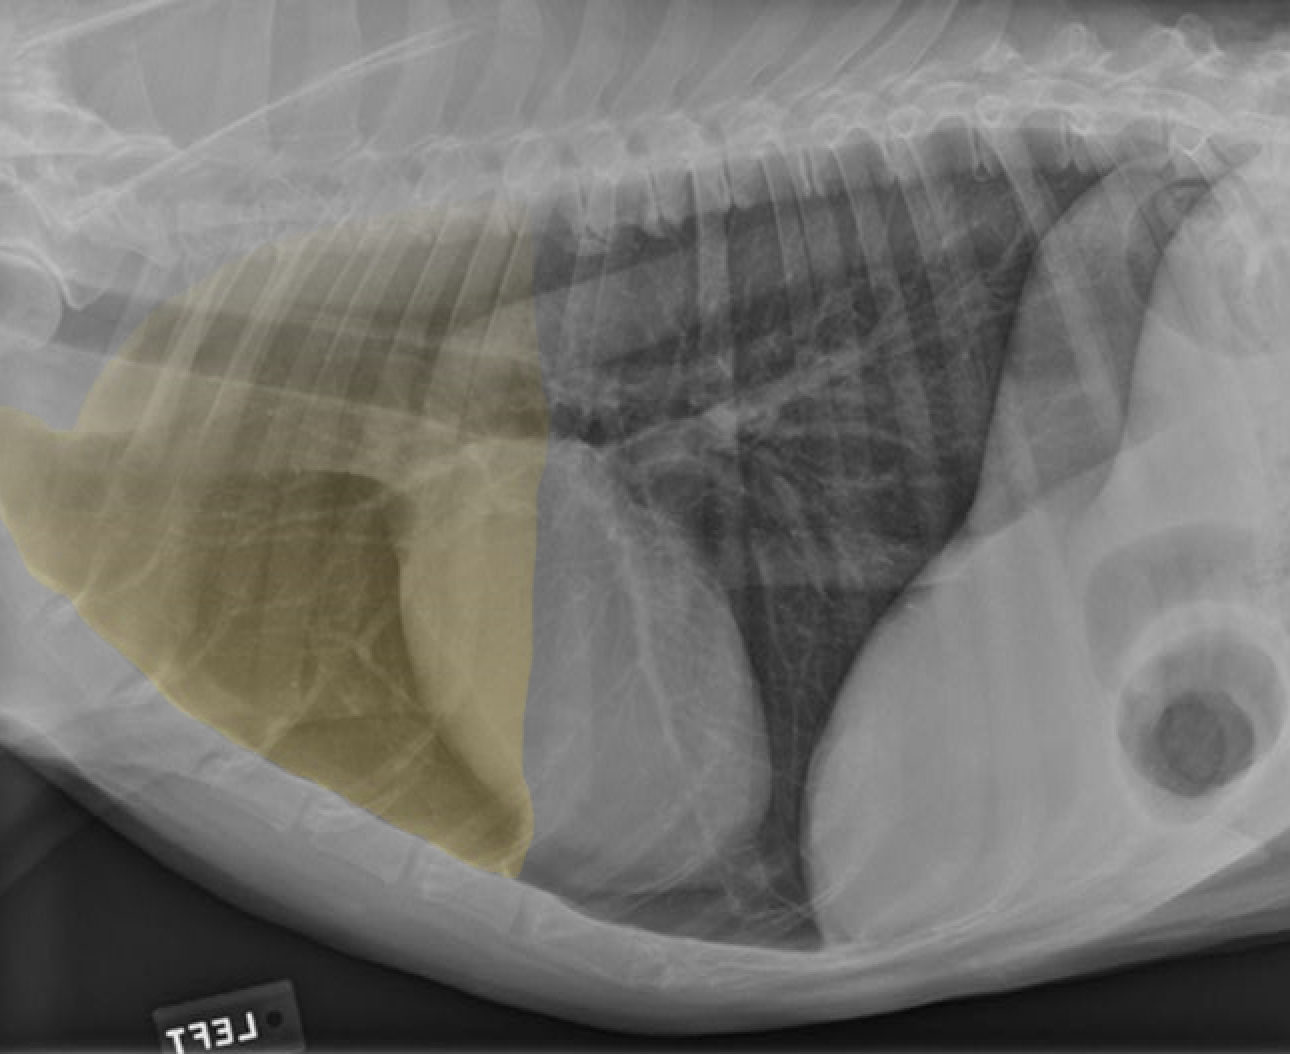

identify the structures of the cat thorax

A= heart

B= diaphragm

C= liver

how does the shape of the cat thorax differ than the dogs

shape: narrow and steep, heart sits more at an angle and it is positioned more caudally (4th-7th intercostal space) also little of the heart is covered by the forelimb as the triceps reaches no further than the 4th rib